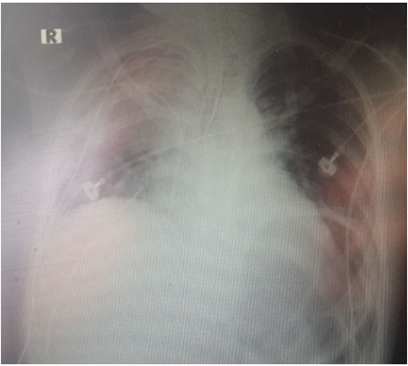

During the operation, the patient presented an inability to spontaneously ventilate with glucose of 220mg/dl, so he remained in sedation and later entered the Intensive Care Unit with a BP: 93/63, HR: 103 and RR: 12 (with mechanical ventilation) with rhonchi and rough breathing for postoperative management. With this evaluation, the diagnosis of Acute Respiratory Failure, decompensated type I diabetes mellitus and septic shock to pulmonary focus is reached. The necessary management was carried out and the patient presented a favorable recovery with respiratory physiotherapy and pulmocare 1 can every 12hrs that contributed to the extubation of the patient, but 2 days later he began to present compromise of the sensorium state with a BP: 80/50, HR : 130 and glucose values ​​of 350 to 450mg / dl plus a metabolic acidosis, a control chest X-ray is requested (Figure 3) and the diagnoses previously raised are handled again this time without patient improvement apart from vasopressor support, 3 days later he presented a BP: 170/90, HR: 150 with Ventricular Tachycardia evolving to Ventricular Fibrillation and despite the efforts to stabilize it, he died in the ICU.

Figure 3 Plain chest X-ray, evidence of radiopacity in both lung fields (white arrows) corresponding to a pattern with air bronchogram and slight mediastinal widening.